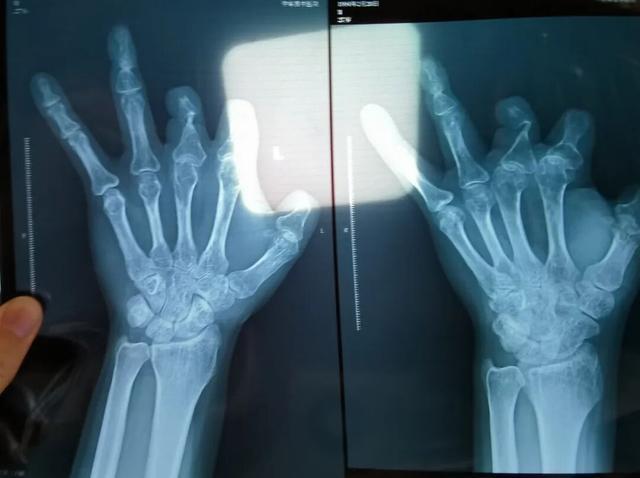

患者王海森左手拇指关节以上部位被电锯切断,收费单显示术中使用了微血管吻合装置,但X光片中未显示该器械。新京报记者 程亚龙 摄

该产品的代理商曾向新京报记者证实,微血管吻合装置为植入型医疗器材,患者拍摄X光片时会有显示。新京报记者获取了一位曾在郑大一附院接受手术、使用了该产品的患者的X光片,其手术部位可见一绿豆大小的光圈。

单价1.68万元,声称在术中植入体内、用于缝合血管的两个环形吻合装置,竟然在王海森的X光片上消失了。

2021年12月,患者彭先生拍摄的左手X光片,未见收费单据中列出的微血管吻合装置。新京报记者 程亚龙 摄

装置上带有不锈钢针,不可能被人体吸收,唯一的可能就是“手术时其实没有使用”。尽管之前也有其他人向王海森透露过这一点,但直到看到片子前,他一直都不相信。